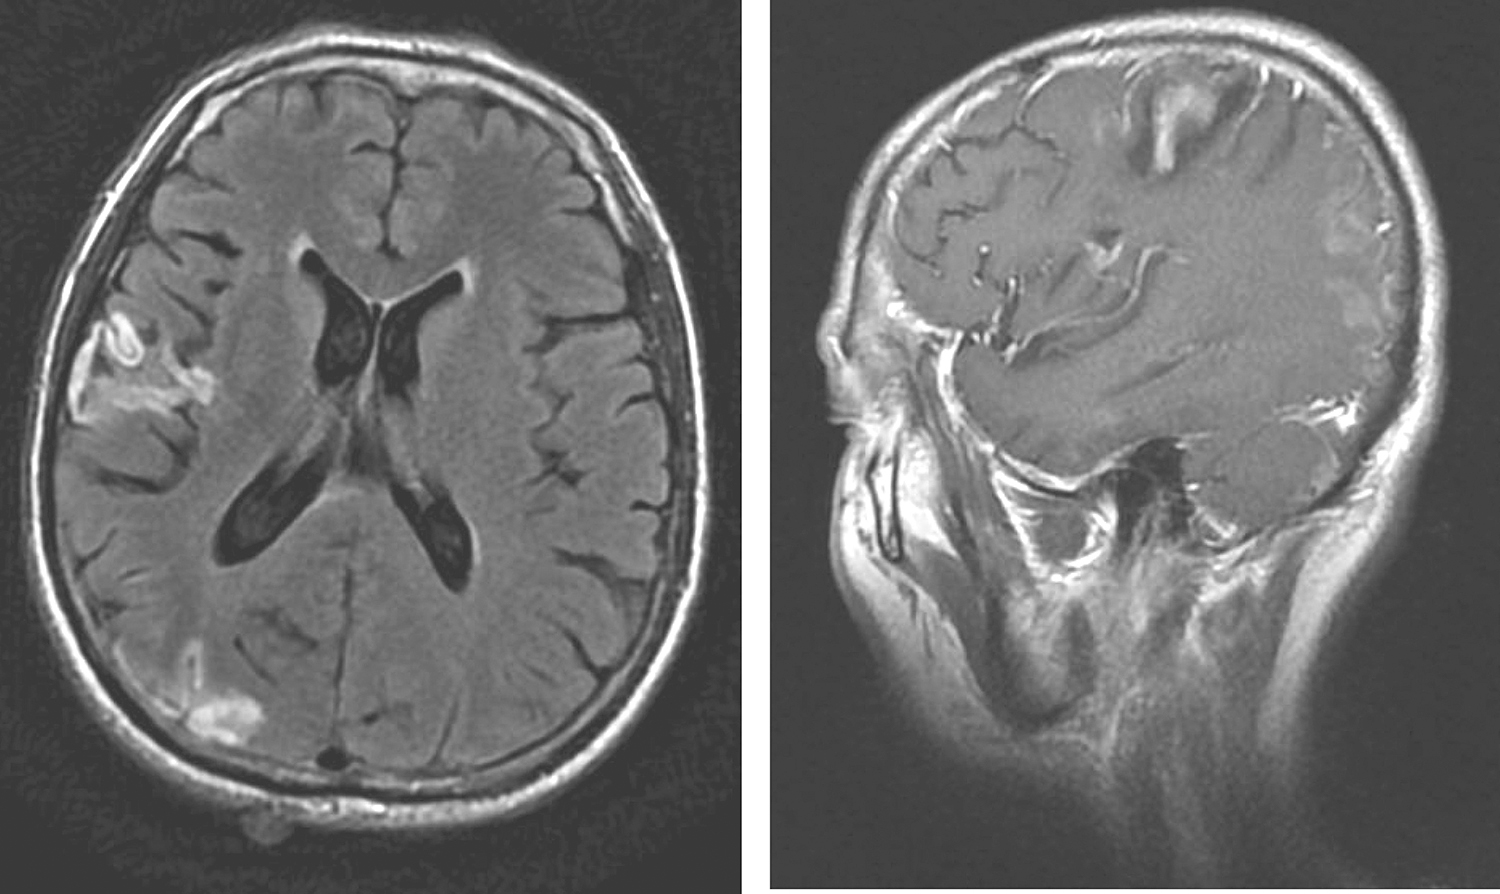

7.2013年8月16日颅脑MR 右侧大脑额、颞、顶叶及枕叶皮质及皮质下可见多发片状异常信号(图5),呈脑回样改变,T2WI/FLAIR呈高信号,增强扫描部分呈片状条状强化,局部脑沟变宽。左侧大脑半球、小脑、脑桥未见明显异常强化结节和肿物影。双侧脑室系统基本对称,未见明确扩张和移位,中线结构居中。

图5 颅脑MRI示右侧大脑额、颞、顶叶及枕叶皮质及皮质下多发片状异常信号

影像学诊断:右侧大脑额、颞、顶叶及枕叶区多发异常信号影,考虑为多发脑梗死,请结合临床。